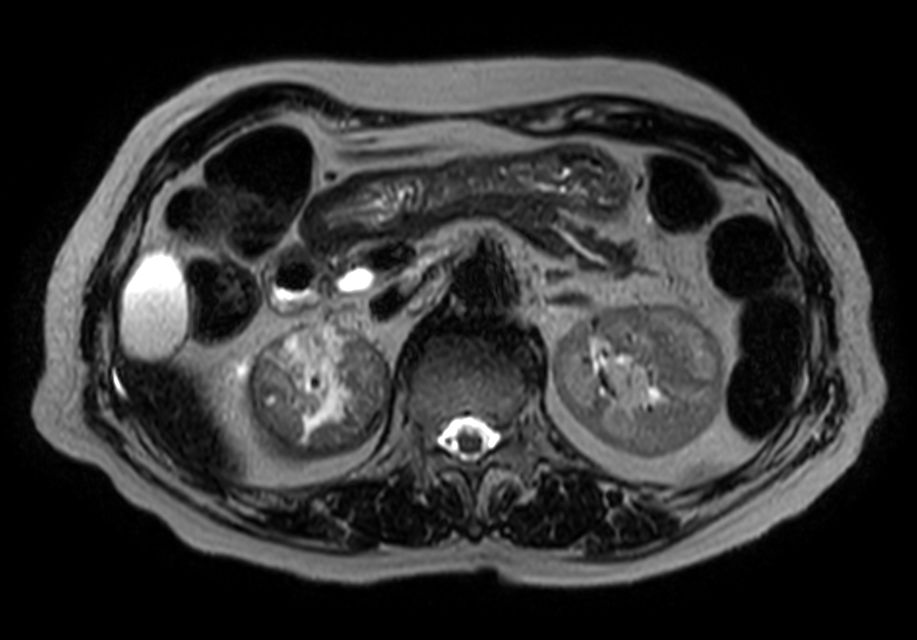

Patient with renal failure. ExamCard includes MultiVane XD to acquire motion-free diagnostic images and 4D FreeBreathing to perform multi-phase contrast-enhanced MRI studies.

Heavy T2w TSE - Free Breathing